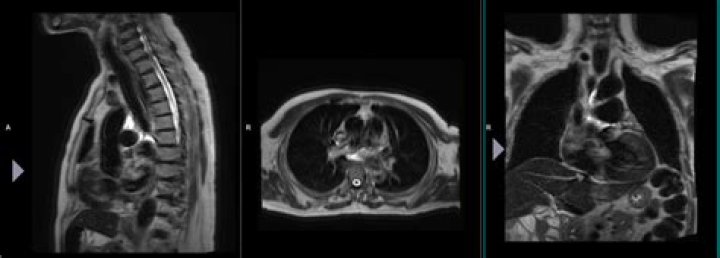

Localizer scans. A set of three-plane, low-resolution, large field-of view localizers are first obtained, equivalent to “scout views” in CT. These localizer images will be used for plotting slices in step 6. 5.

Localizer images, also called scout images, are used in MR and CT studies to identify the relative anatomical position of a collection of cross-sectional images. A localizer can be acquired as a separate image, as is often done for CTs, or it can be dynamically generated, as is done for MRs.

This coordinate system consists of three planes to describe the standard anatomical position of a human. The basic orientation terms for a MRI of the body taken: From the side would be a sagittal plane; from the front, would be a coronal plane; and from the top down, would be a transverse plane.